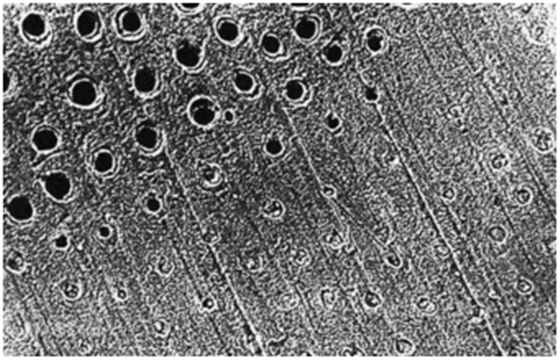

牙本質(zhì)切削后牙本質(zhì)縱斷面,可見牙本質(zhì)小管中存在玷污層栓(放大倍數(shù)2000)

詳細了解自酸蝕、全酸蝕

圖中上半部分牙本質(zhì)采用37%磷酸酸蝕15秒徹底沖洗后牙本質(zhì)橫斷面,可見玷污層已經(jīng)被去除(放大倍數(shù)1000)

牙本質(zhì)縱斷面。管周牙本質(zhì)被去除,管間牙本質(zhì)膠原纖維暴露(放大倍數(shù)5000)